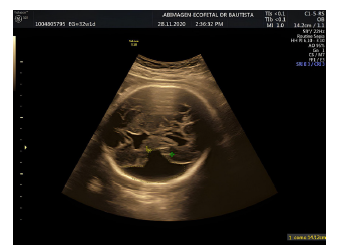

Paciente primigestante de 18 años de edad, sin antecedentes de infección por TORCH, quien asiste a sus controles prenatales con curso normal y sin alteraciones fetales en el Sistema Nervioso Central (SNC) hasta la semana 21,6 de gestación (ver figura 1). Durante la semana 30 de gestación se sospecha, por ecografía prenatal, de una alteración del SNC; se obtiene una imagen anecoica de 35 x 37 mm en la porción central del hemisferio central izquierdo, que comunica la cavidad ventricular con el espacio subaracnoideo (ver figura 2).

Fuente: autores.

Figura 2 Ecografía en corte transversal a nivel de la cabeza fetal, en el diámetro biparietal; se sospecha de alteración neurológica compatible con esquizencefalia tipo II.